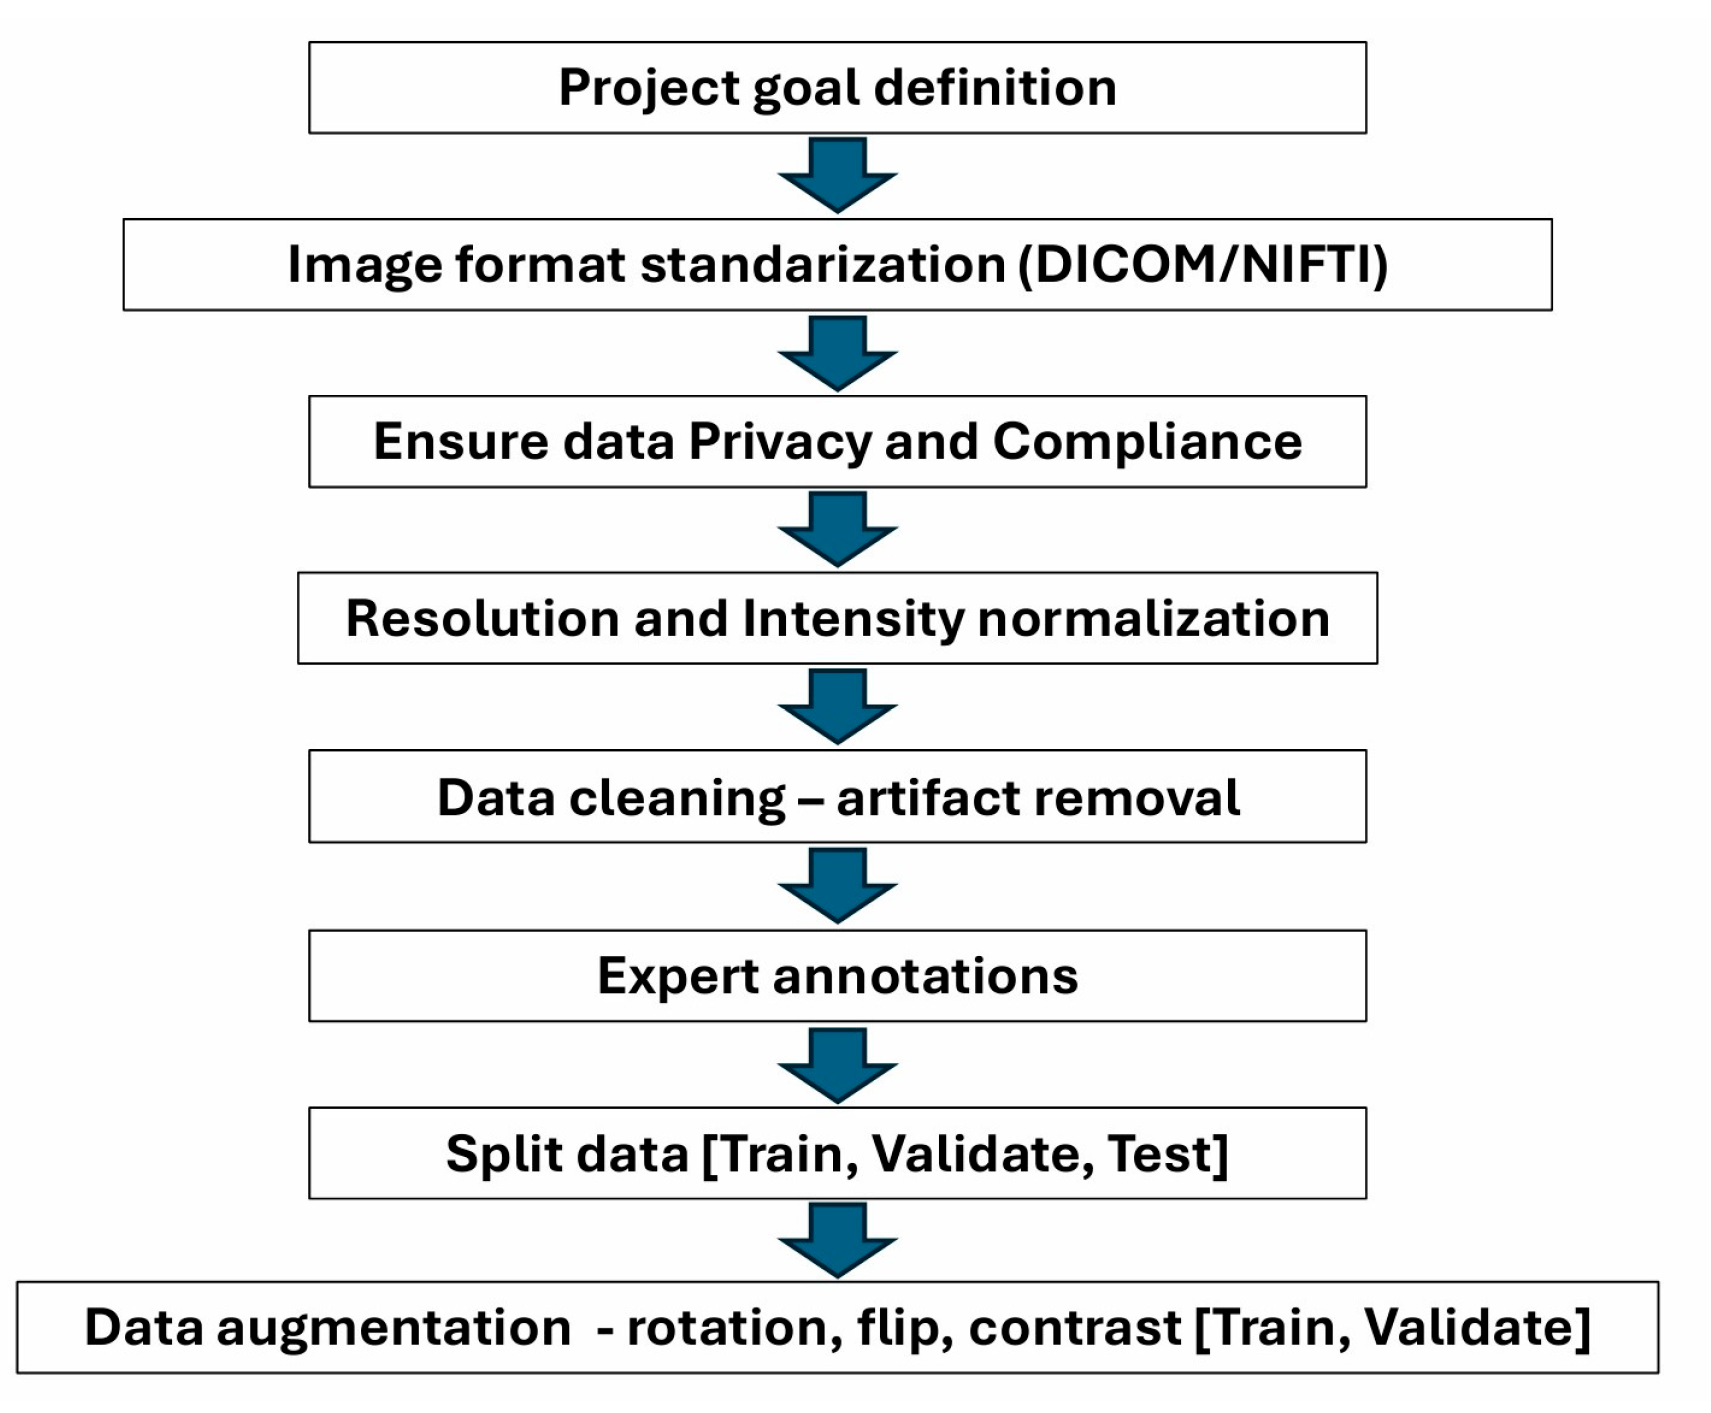

6. Importance of Data Preparation for Processing with AI